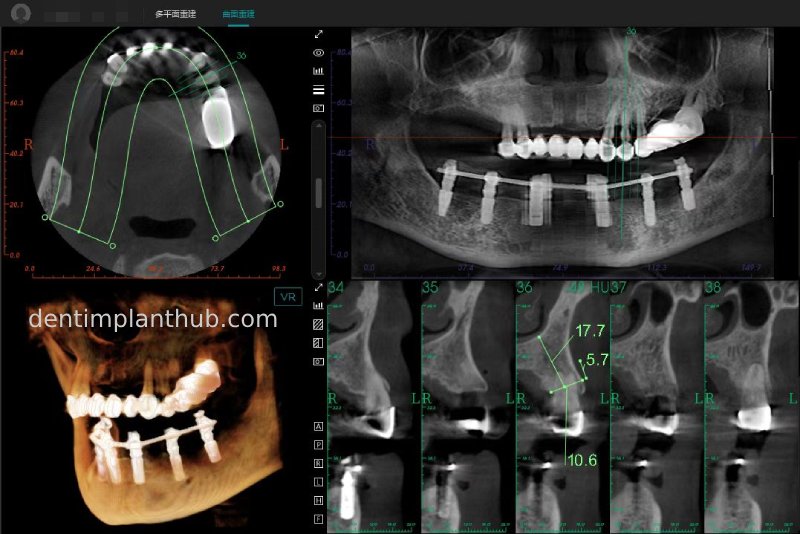

Post-surgical CBCT review photos

16

14

12

22

24

26